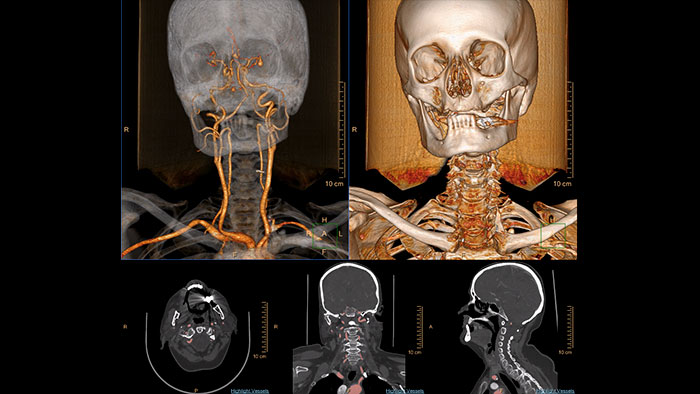

Multi Modality Advanced Vessel Analysis (AVA)

Comprehensive vascular analysis planning

Designed to examine and quantify different types of vascular lesions from CTA and MRA scans. It accommodates different modes of inspection, allows labeling different vascular lesions, and helps navigating through multiple findings.

Demonstrated to reduce the post-processing time by 50% when compared to manual Head & Neck CT angiography (CTA) analysis*.

Benefits

- Ability to choose which Head & Neck Bone Removal method to be used (Standard vs. Smooth).

- Customizable Volume rendering “smoothness” for the 3D Head & Neck vascular structure using a smoothness control.

* Ardley N et al. Efficacy of a new post processing workflow for CTA head and neck. ECR 2013 / C-1760.